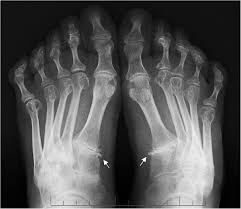

The rheumatoid community on reddit. For more information and past images of the month, go to. These tests primarily look for bone damage in the patient's joints caused by the inflammation associated with ra. The 2010 rheumatoid arthritis classification criteria help doctors diagnose rheumatoid arthritis. It is caused when the immune system (the body's defense system) is not working properly. The earliest manifestation of rheumatoid arthritis of the forefoot is synovitis of the mtp joints with eventual hyperextension deformity of the mtp joints including distal. Sorptiometry should be performed to diagnose. It typically results in warm, swollen, and painful joints.

The rheumatoid community on reddit. The earliest manifestation of rheumatoid arthritis of the forefoot is synovitis of the mtp joints with eventual hyperextension deformity of the mtp joints including distal. Rheumatoid arthritis (ra) imaging tests are used to look for signs of ra and to monitor the disease's progression. (uk) national rheumatoid arthritis society helpline. </b>small joints of the feet, wrists, and hands are frequently involved by a reduction of osteoporosis; Rheumatoid arthritis (ra) is a chronic autoimmune multisystemic inflammatory disease that affects many organs but predominantly attacks the synovial tissues and joints. Rheumatoid arthritis (ra) is the most common type of autoimmune arthritis. Rheumatoid arthritis is considered an indication for resurfacing of the patella during total knee arthroplasty.

If the pattern of disease is not symmetrical, then a different diagnosis should be considered. In rheumatoid arthritis, the body's immune system attacks its own healthy cells inside certain joints, leading to an inflammatory response. For more information and past images of the month, go to. However, they are not useful in the early stages of rheumatoid arthritis, before joint damage occurs. </b>rheumatoid arthritis (ra) is a polyarticular disease with bilateral and symmetric distribution. Sorptiometry should be performed to diagnose. The rheumatoid community on reddit. Rheumatoid arthritis (present for >10 years). The ulnar styloid is destroyed with the rest of the distal ulna (white arrow), there is destruction of the carpal bones (yellow arrow) and there is dislocation of the 1st metacarpal on the destroyed trapezium. Rheumatoid arthritis affects around 400,000 adults aged 16 and over in the uk. Reddit gives you the best of the internet in one place. Ra causes pain, swelling, stiffness, and loss of function in joints. The earliest manifestation of rheumatoid arthritis of the forefoot is synovitis of the mtp joints with eventual hyperextension deformity of the mtp joints including distal.